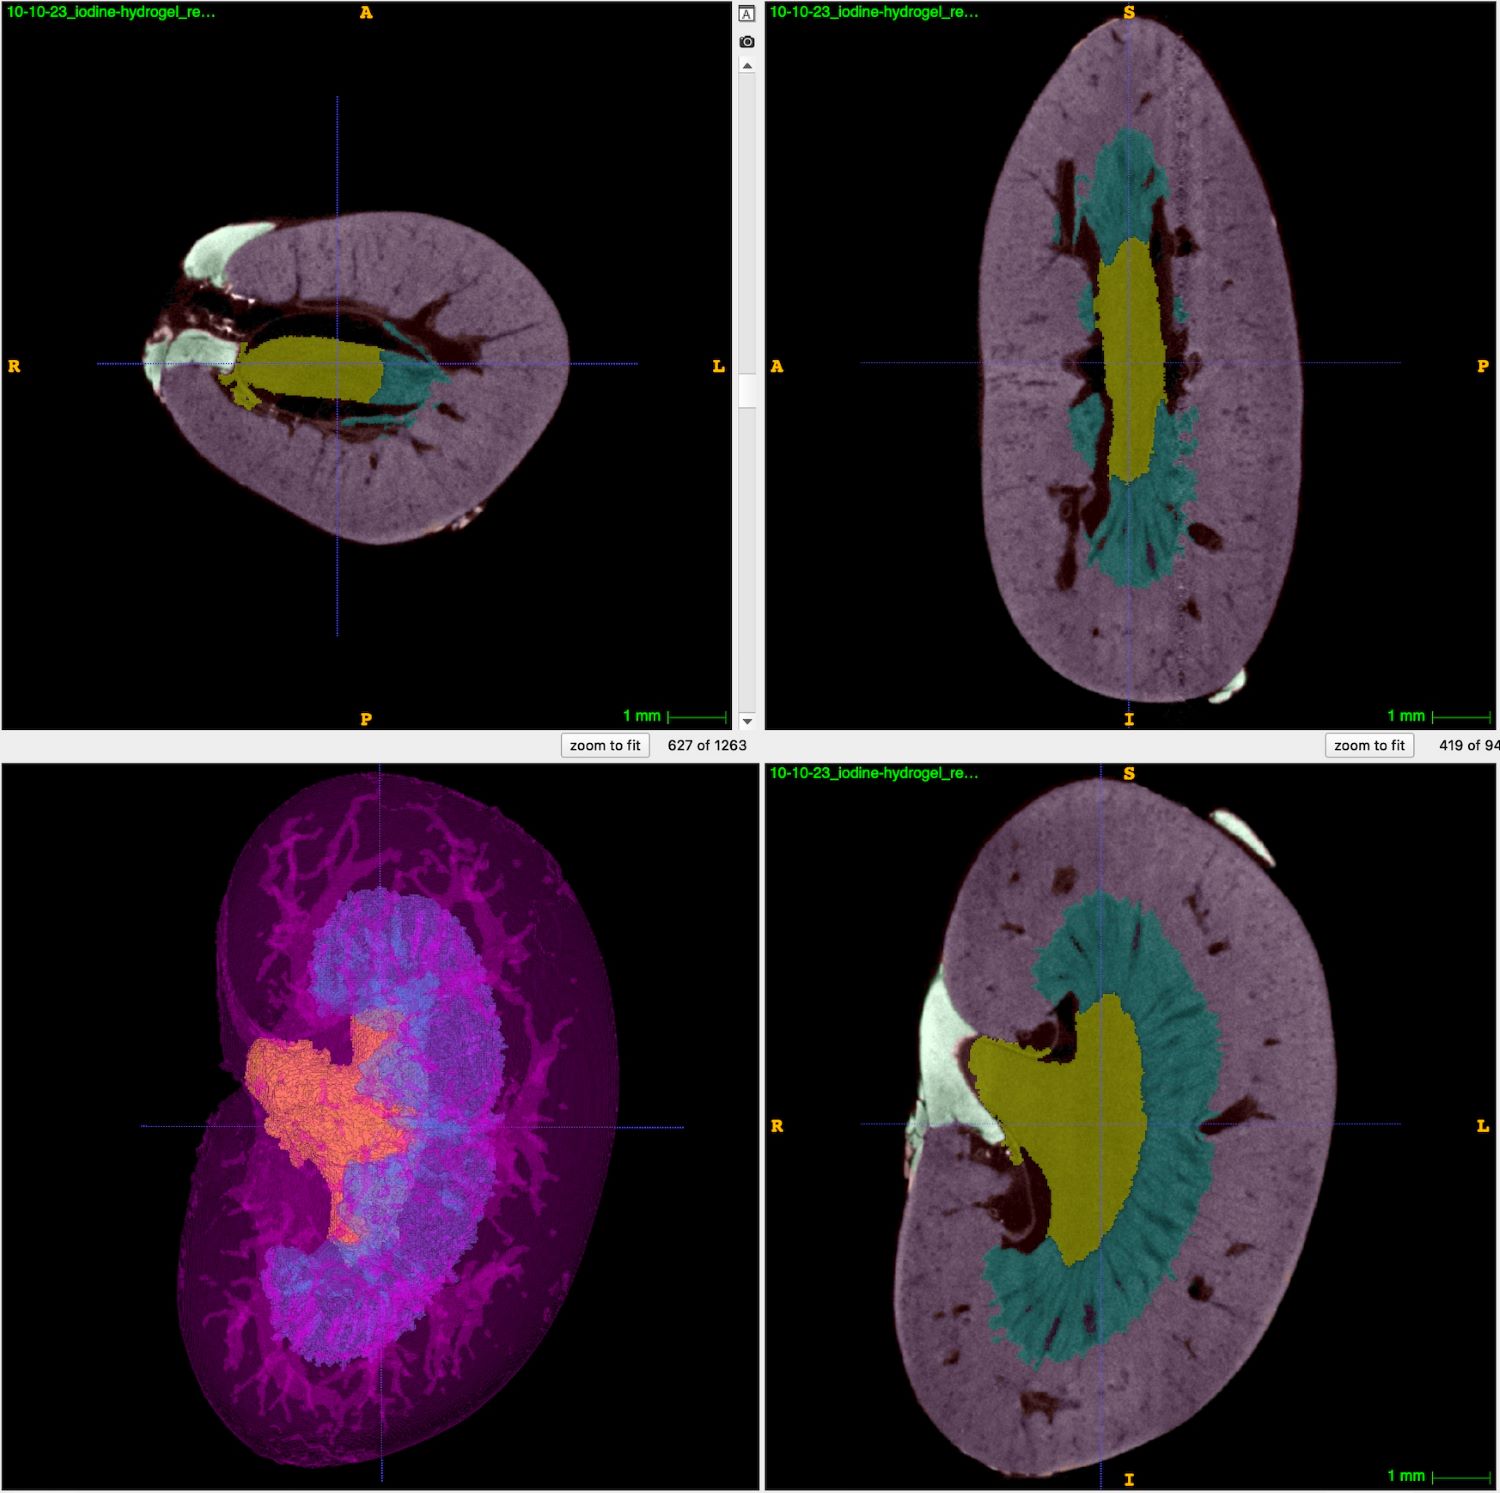

Mouse kidney with iodine contrast (Photo: Marrelli Lab)